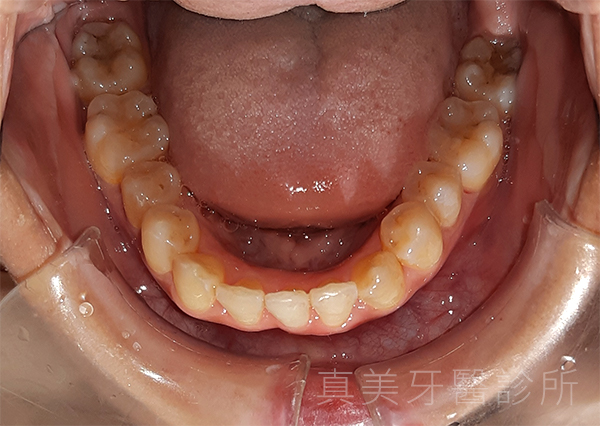

經過療程後,洪小姐的牙齒排列整齊了許多,原本外凸的門牙消失了,牙弓也變得更寬更自然。她開心地說,現在不但更喜歡照鏡子,也在合照時勇敢露齒微笑,甚至開始更積極參與各種社交場合。